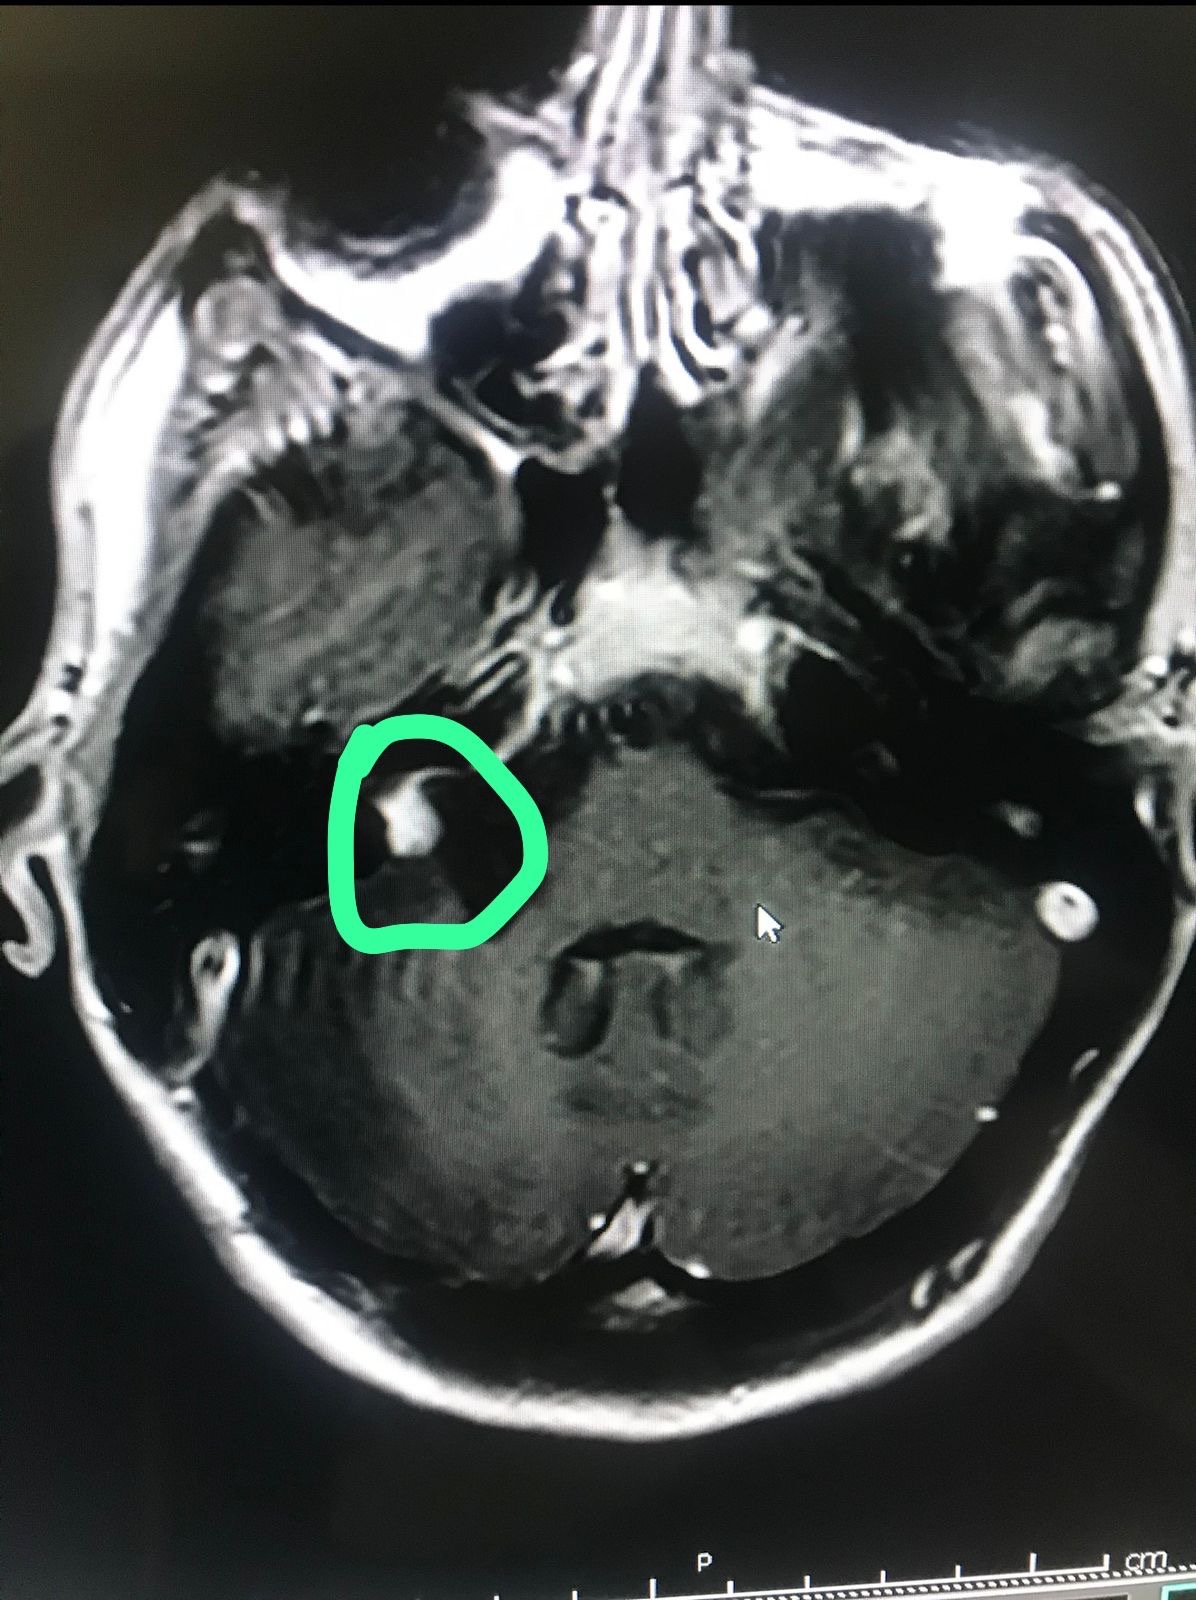

Në vitin 2025, rezonanca magnetike tregoi një tumor të mbetur me përmasa 14×12×10 mm.

Në janar 2026, tumori është rritur në 19×18×15 mm, që do të thotë një rritje rreth 5 mm vetëm brenda një viti.

Sot kam humbur plotësisht dëgjimin në veshin e djathtë dhe tumori vazhdon të rritet.

Mjekët më kanë rekomanduar trajtim urgjent me radiokirurgji të avancuar, për të ndaluar rritjen e tumorit para se situata të bëhet më e rrezikshme.

Koha është shumë e rëndësishme, sepse tumori po rritet shpejt. Nëse nuk arrij ta trajtoj në kohë, mund të detyrohem të bëj një operacion të katërt në tru, i cili ka rrezik shumë të madh për shkak të ndërhyrjeve të mëparshme.